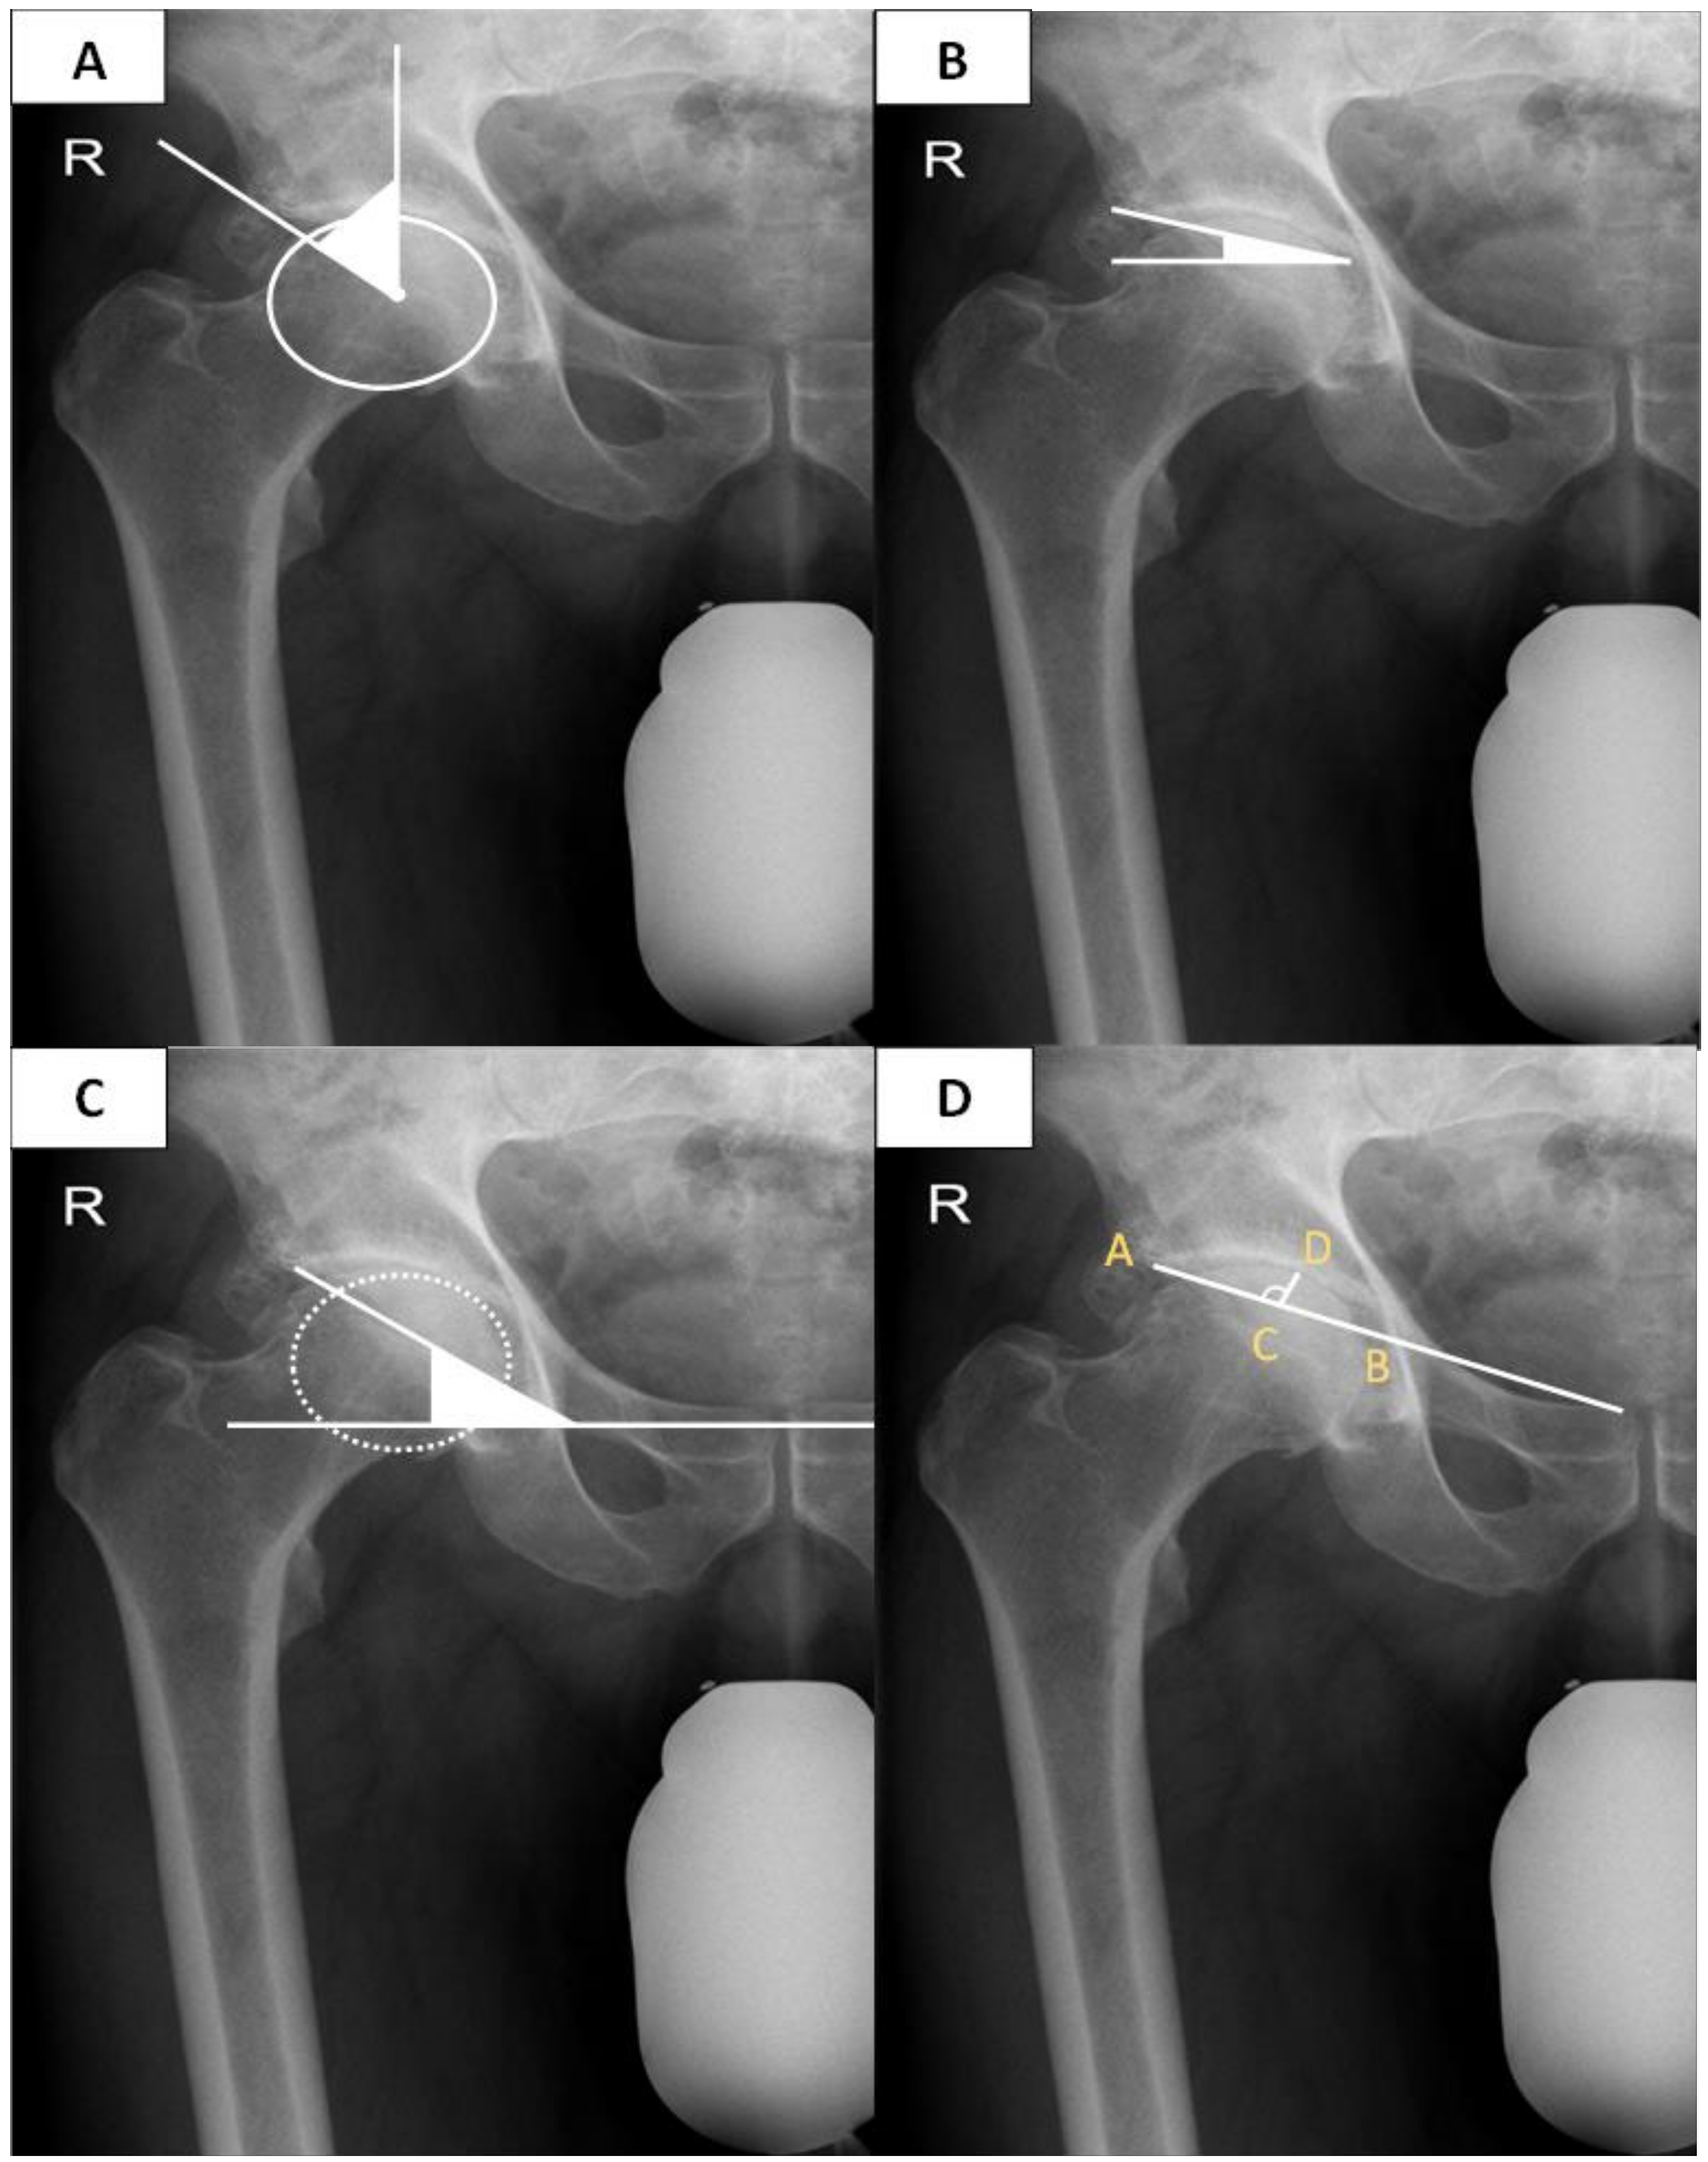

| LCEA (mean ± SD) | 40.41° ± 9.82° | 55.09° ± 9.64° | <0.00 |

| Sharp (mean ± SD) | 36.44° ± 5.15° | 34.04° ± 4.81° | <0.00 |

| Tönnis (mean ± SD) | 6.16° ± 5.70° | 3.12° ± 5.89° | <0.00 |

| Acetabular depth (mean ± SD) | 24.73 mm ± 4.01 mm | 27.92 mm ± 4.67 mm | <0.00 |

| ADWR (mean ± SD) | 334.60 ± 43.33 | 388.50 ± 61.22 | <0.00 |

| Change of FO (preoperative vs. postoperative) (mean ± SD) | 4.11 mm ± 7.66 mm | 0.71 mm ± 8.21 mm | <0.00 |

| FO, preoperative (mean ± SD) | 42.94 mm ± 7.20 mm | 46.22 mm ± 7.57 mm | <0.00 |

| FO, postoperative | 47.05 mm ± 5.38 mm | 45.52 mm ± 4.46 mm | 0.03 |

| LLD, preoperative (mean ± SD) | 4.49 mm ± 4.24 mm | 7.65 mm ± 6.76 mm | <0.00 |

| LLD, postoperative (mean ± SD) | 4.87 mm ± 4.12 mm | 5.41 mm ± 5.00 mm | 0.41 |

| AGVD (mean ± SD) | 108.59 mm ± 13.75 mm | 101.91 mm ± 14.36 mm | <0.00 |

| GT/ASIS (mean ± SD) | 1.19 ± 0.07 | 1.13 ± 0.07 | <0.00 |

| Cup inclination | 36.57° ± 6.57° | 38.13° ± 6.82° | 0.04 |